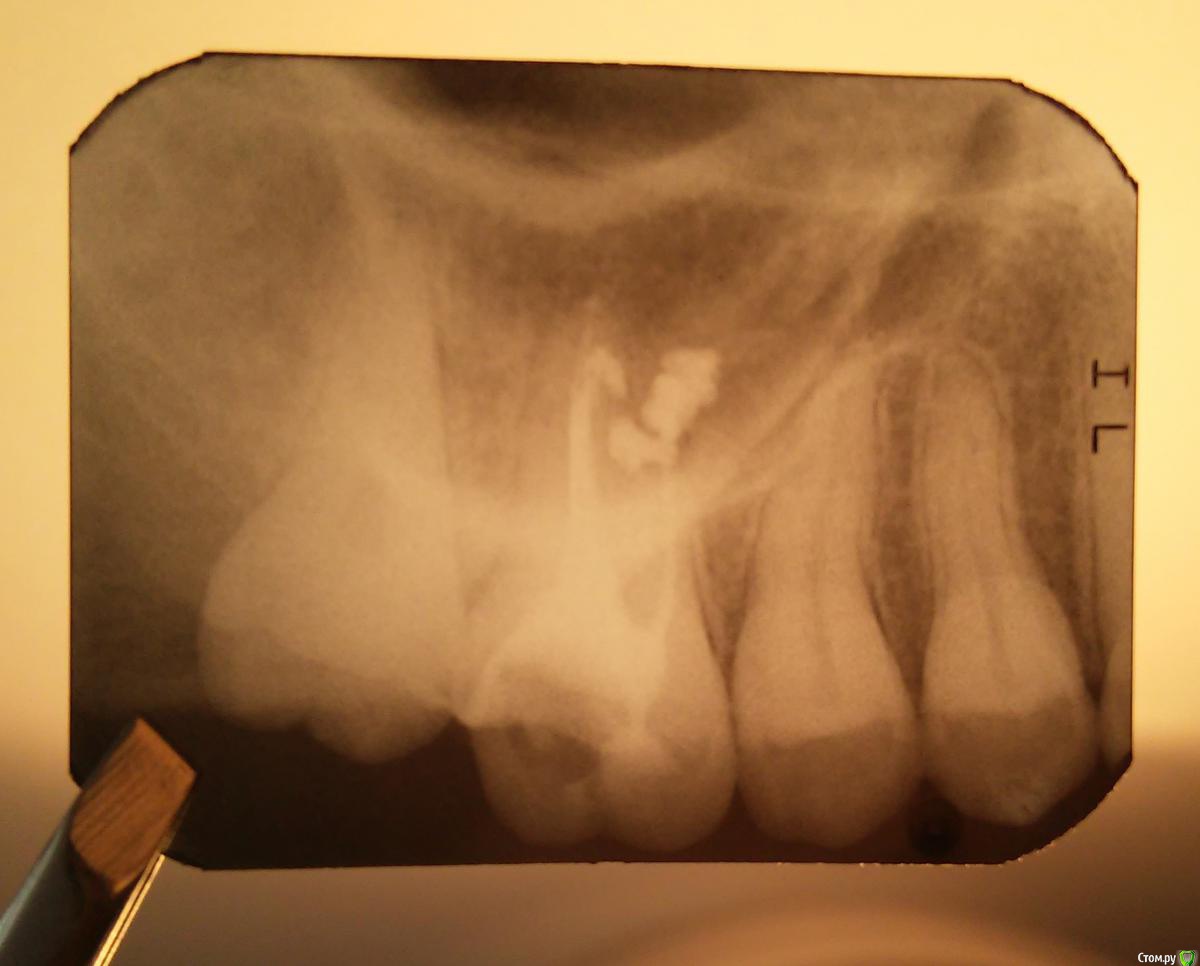

Coffee Опубликовано 6 сентября, 2015 Поделиться Опубликовано 6 сентября, 2015 Здравствуйте!Залечила зуб, стоматолог удалила нерв, запломбировала каналы и отправила на снимок зуба. Снимок прилагается.На снимке стоматолога нечего не смутило и она завершила свою работу. Лекарство, которое должно было удалить нерв, находилось в зубе с 14 августа по 1 сентября. Но при работе в одном из каналов было предельно трудно терпеть боль. Сейчас зуб очень чувствителен, при постукивании по нем и при надавливании болит. Да и без "дотрагиваний" до него ощущения немного болезненные в той области, такое ощущение, что там что-то воспалено.Подскажите пожалуйста, все ли нормально с этим зубом. Как-то меня немного смутил снимок, но я не специалист в этом совершенно, может так должно быть? Все ли нормально с корнями этого зуба? Ссылка на комментарий

faity Опубликовано 6 сентября, 2015 Поделиться Опубликовано 6 сентября, 2015 снимок так себе, если есть чувствительность, скорее всего пропущена анатомия. а вот паф(облако за корнями) не страшен, ну или не сильно страшен. 3 Ссылка на комментарий